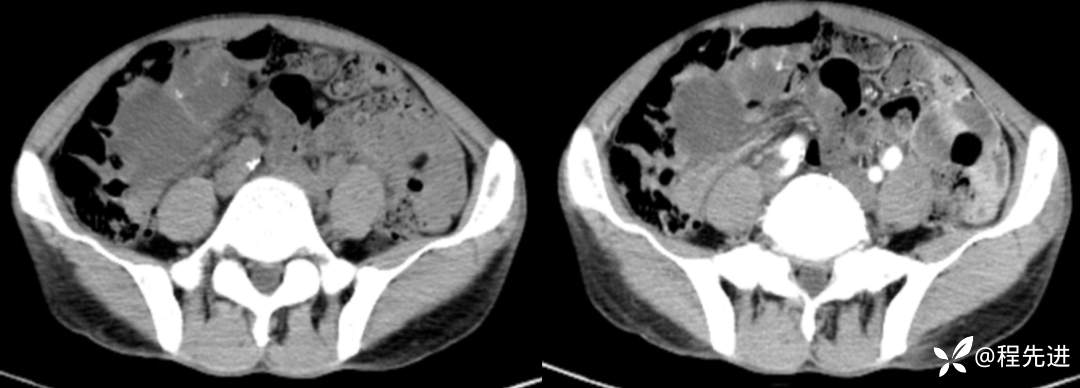

CT平扫+增强

左平扫,右增强